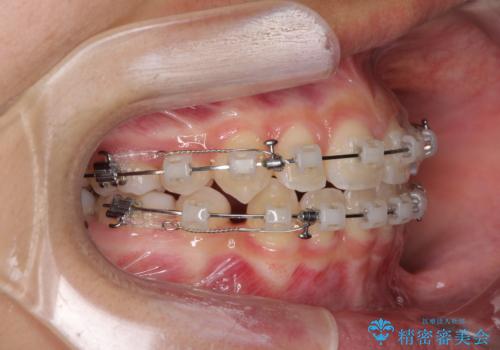

- クリアブラケット

- 2年4ヶ月

当初は八重歯やデコボコが一番気になっていましたが、抜歯矯正により口元の突出感が改善されるにつれ、口の閉じやすさを実感するようになってきました。

部活動で調整来院に来られないことがしばしばあり、期間は予定よりもかかりましたが、きれいに仕上げることができました。